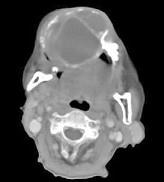

问题 男性,38岁,右侧下颌骨渐进性膨大半年,近来牙齿松动脱落,CT扫描如图所示,请选择最佳答案()

选项 A.动脉瘤样骨囊肿 B.造釉细胞瘤 C.骨软骨瘤 D.牙根囊肿 E.牙龈癌

答案 B